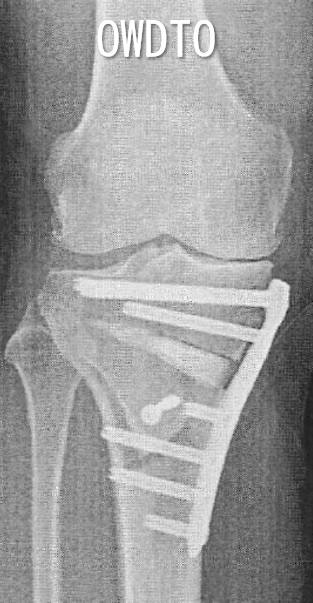

OWDTOの特徴

脛骨の骨切りに対して、脛骨粗面の遠位側で円弧状に骨切りします。

PF関節の位置が変わりません。

膝蓋骨低位がおきません。

膝蓋腱周囲に侵襲がありません。

デメリット

脛骨粗面に固定スクリュー1本追加

後療法をやや遅らせます(免荷1週)。